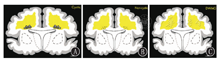

3.6 早产儿脑损伤[15,16,17]早产儿脑损伤的主要原因是围生期缺氧缺血,经典病理形式是脑室周围-脑室内出血(periventricular-intraventricular hemorrhage,PVL-IVH)和PVL。根据Paneth将早产儿脑损伤分为脑白质损伤(brain white matter damage,WMD)、脑非实质区出血、脑其他部位(小脑、基底核和脑干等)损伤。其中WMD又分为囊性、非囊性和弥散性脑白质病变3种(图15)。

图15

早产儿白质软化类型示意图 A:囊性脑白质病变;B:非囊性脑白质病变;C:弥散性脑白质病变

Figure 15

Schematic diagram of leukomalacia type in premature infants A:cystic periventricular leukomalacia;B:non-cystic periventricular leukomalacia;C:diffuse periventricular leukomalacia